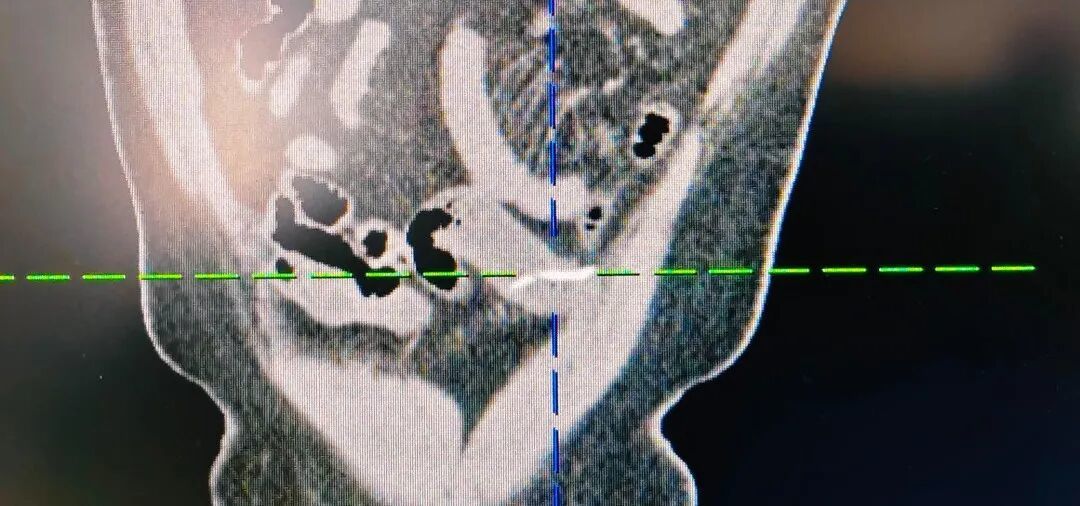

经漳州第三病院普外二科团队详备查验,最终确诊为小肠异物穿孔,而闯下灭顶之灾的,居然是一根不起眼、唯一两三公分长的小鱼刺,普外二科团队为患者行“腹腔镜下小肠离散修补+异物取出术”。